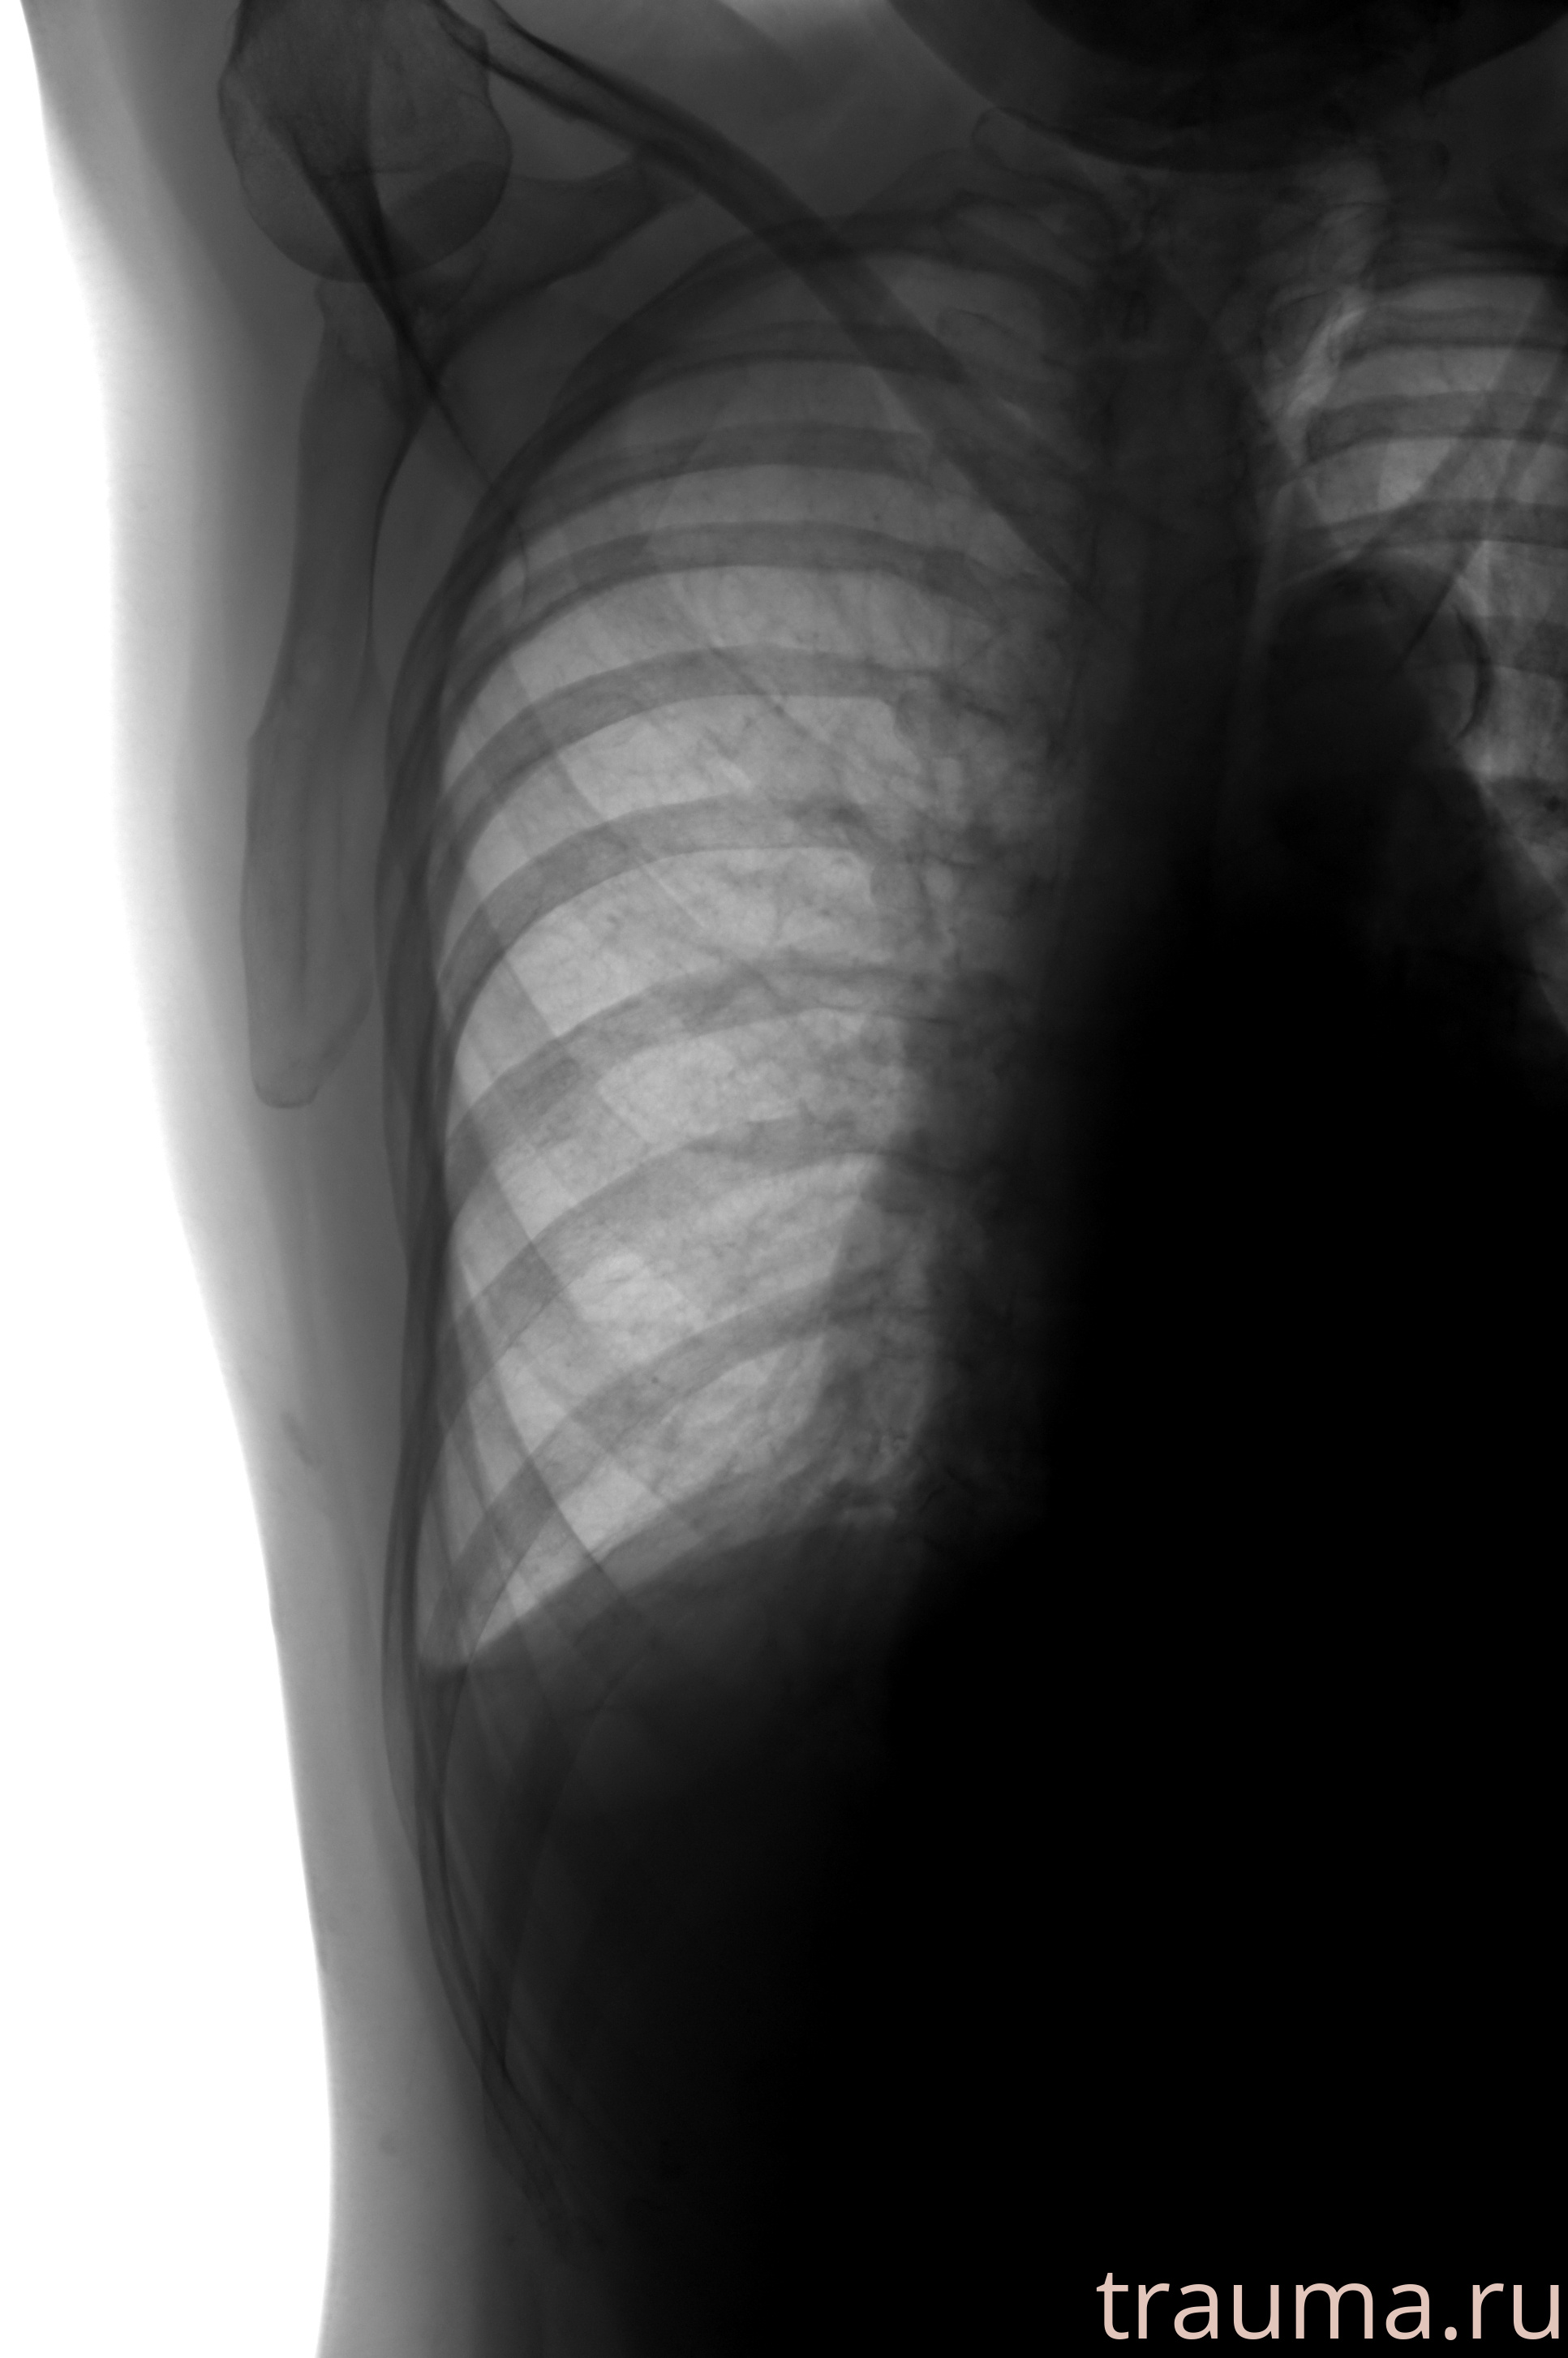

Рентгенограммы

Рентген на дому: по вашему адресу приезжает врач-рентгенолог, травматолог-ортопед с мобильным рентгеновским аппаратом, проводит диагностику травмы или заболевания, делает необходимые рентгенограммы, дает рекомендации по дальнейшему лечению. Получить качественные снимки в домашних условиях возможно благодаря уникальной методике, разработанной МосРентген Центром для института  Склифосовского

Яркость: 1   Контраст: 1   Инвертировать: 0 Увеличение: 1

Перетаскивайте мышь вверх/вниз для контраста, влево/право для яркости. Прокрутка колесом изменяет масштаб. Нажмите Сбросить для возврата к исходному изображению. При увеличении держите мышь в той области, которую хотите рассмотреть.